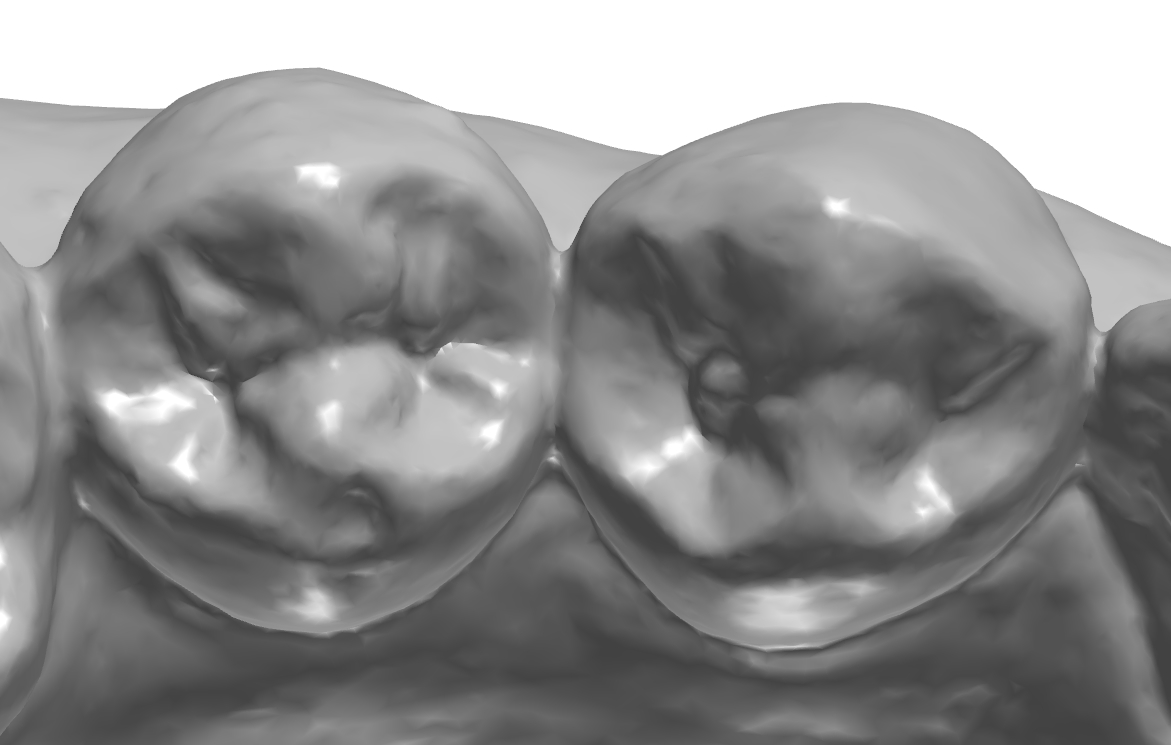

교합면에 형성되어 있는 엠브레져 체크.

설측 교두 체크.

설측 교합면쪽 엠브레져 체크.

교합면 확대.